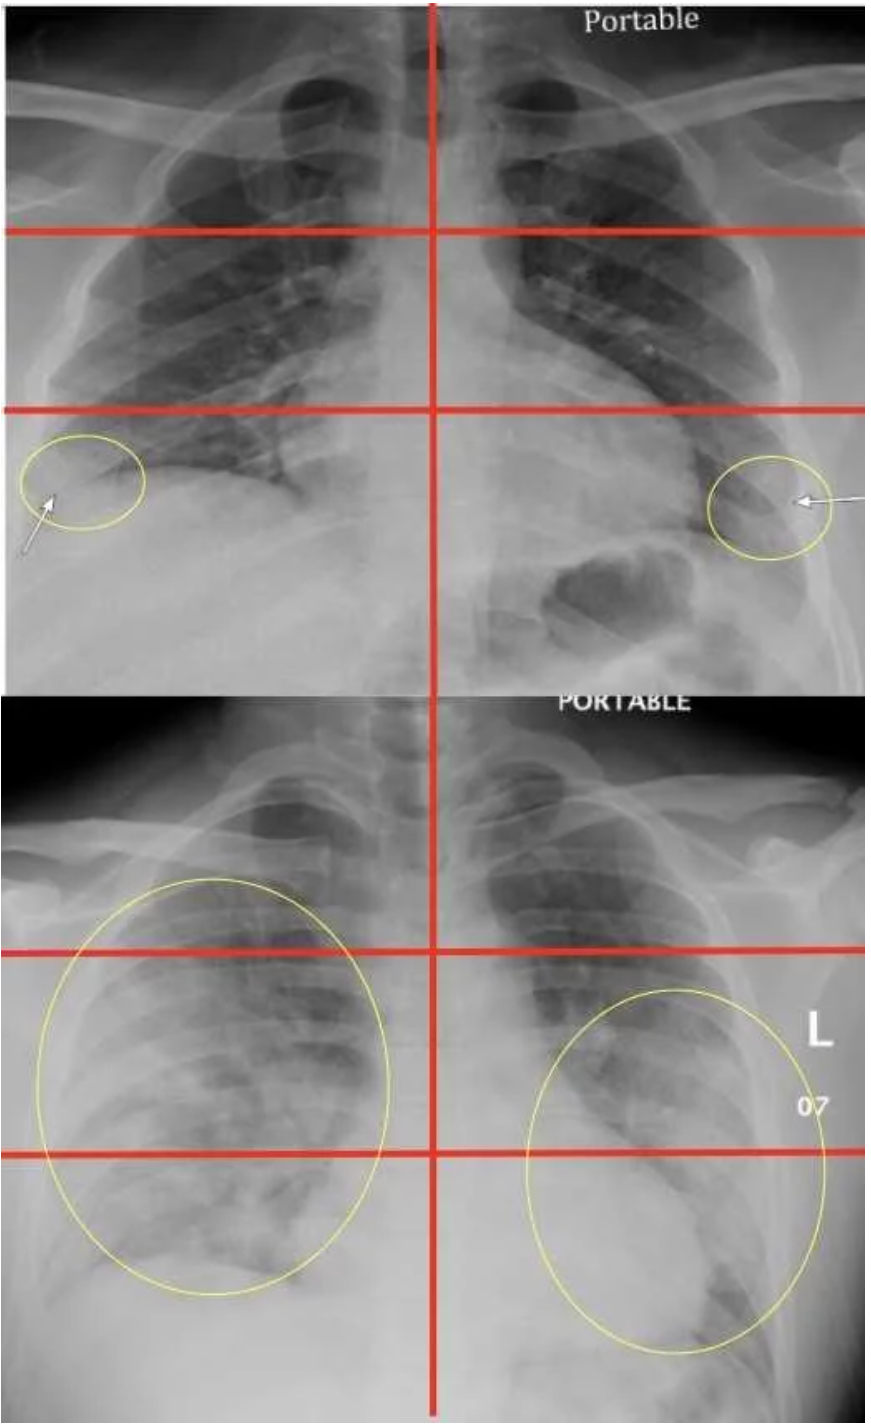

Using a structured reporting approach, radiologists are better able to predict which patients will also have a positive RT-PCR result.

Applying a deep-learning model to a photograph of a chest X-ray can help providers in resource-poor areas diagnose the disease.

A well-trained algorithm can read chest X-rays as well as third-year residents, opening the door for more streamlined workflow and cost savings.